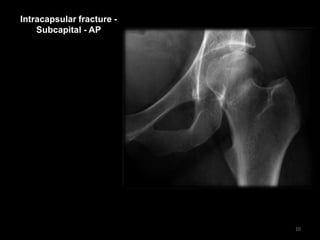

Intracapsular fracture -

Subcapital - AP

10

• Shenton's line is

disrupted

• Increased density of

the femoral neck is

due to overlapping -

impacted bone

• The lesser

trochanter is more

prominent than

usual - due to

external rotation of

the femur

11